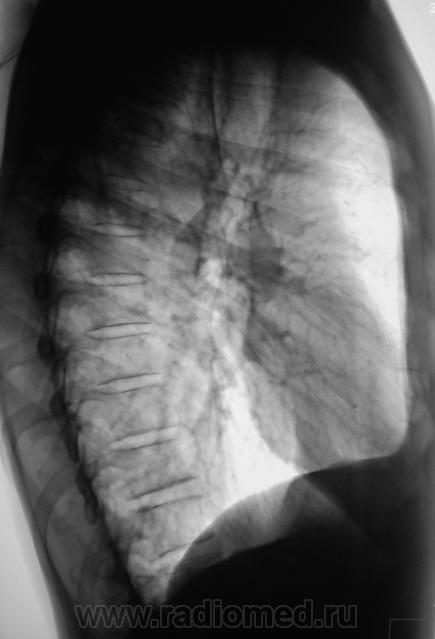

Контроль через 1 месяц после противовоспалительной терапии.